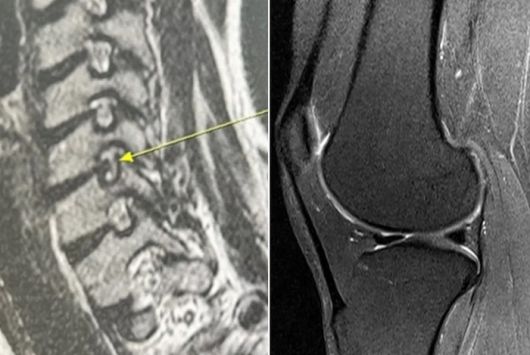

이정현은 9일 자신의 SNS를 통해 “둘째 출산 후 한 달 만에 이미 약속되었던 광고 촬영들을 하고, 대학원 복학과 함께 육아와 집안 살림, 그리고 단편영화 제작까지 겹치며 몸이 완전히 망가졌다”며 “목디스크도 터지고, 25년간 가수 활동을 하며 격렬한 춤을 춰 무릎 연골도 많이 상했고, 모유수유까지 하며 허리디스크까지 왔다”고 고백했다. 이어 “꾸준히 치료받은 덕에 엉망이었던 몸이 완치되어 정말 행복하다”며 건강을 회복한 소감을 전했다.

이정현은 상한 부위의 MRI 사진도 함께 공개했다. 또한 이정현은 정형외과 전문의 남편 박유정씨와 함께 카페에서 음료를 마시며 여유로운 시간을 보내는 사진도 게재했다.